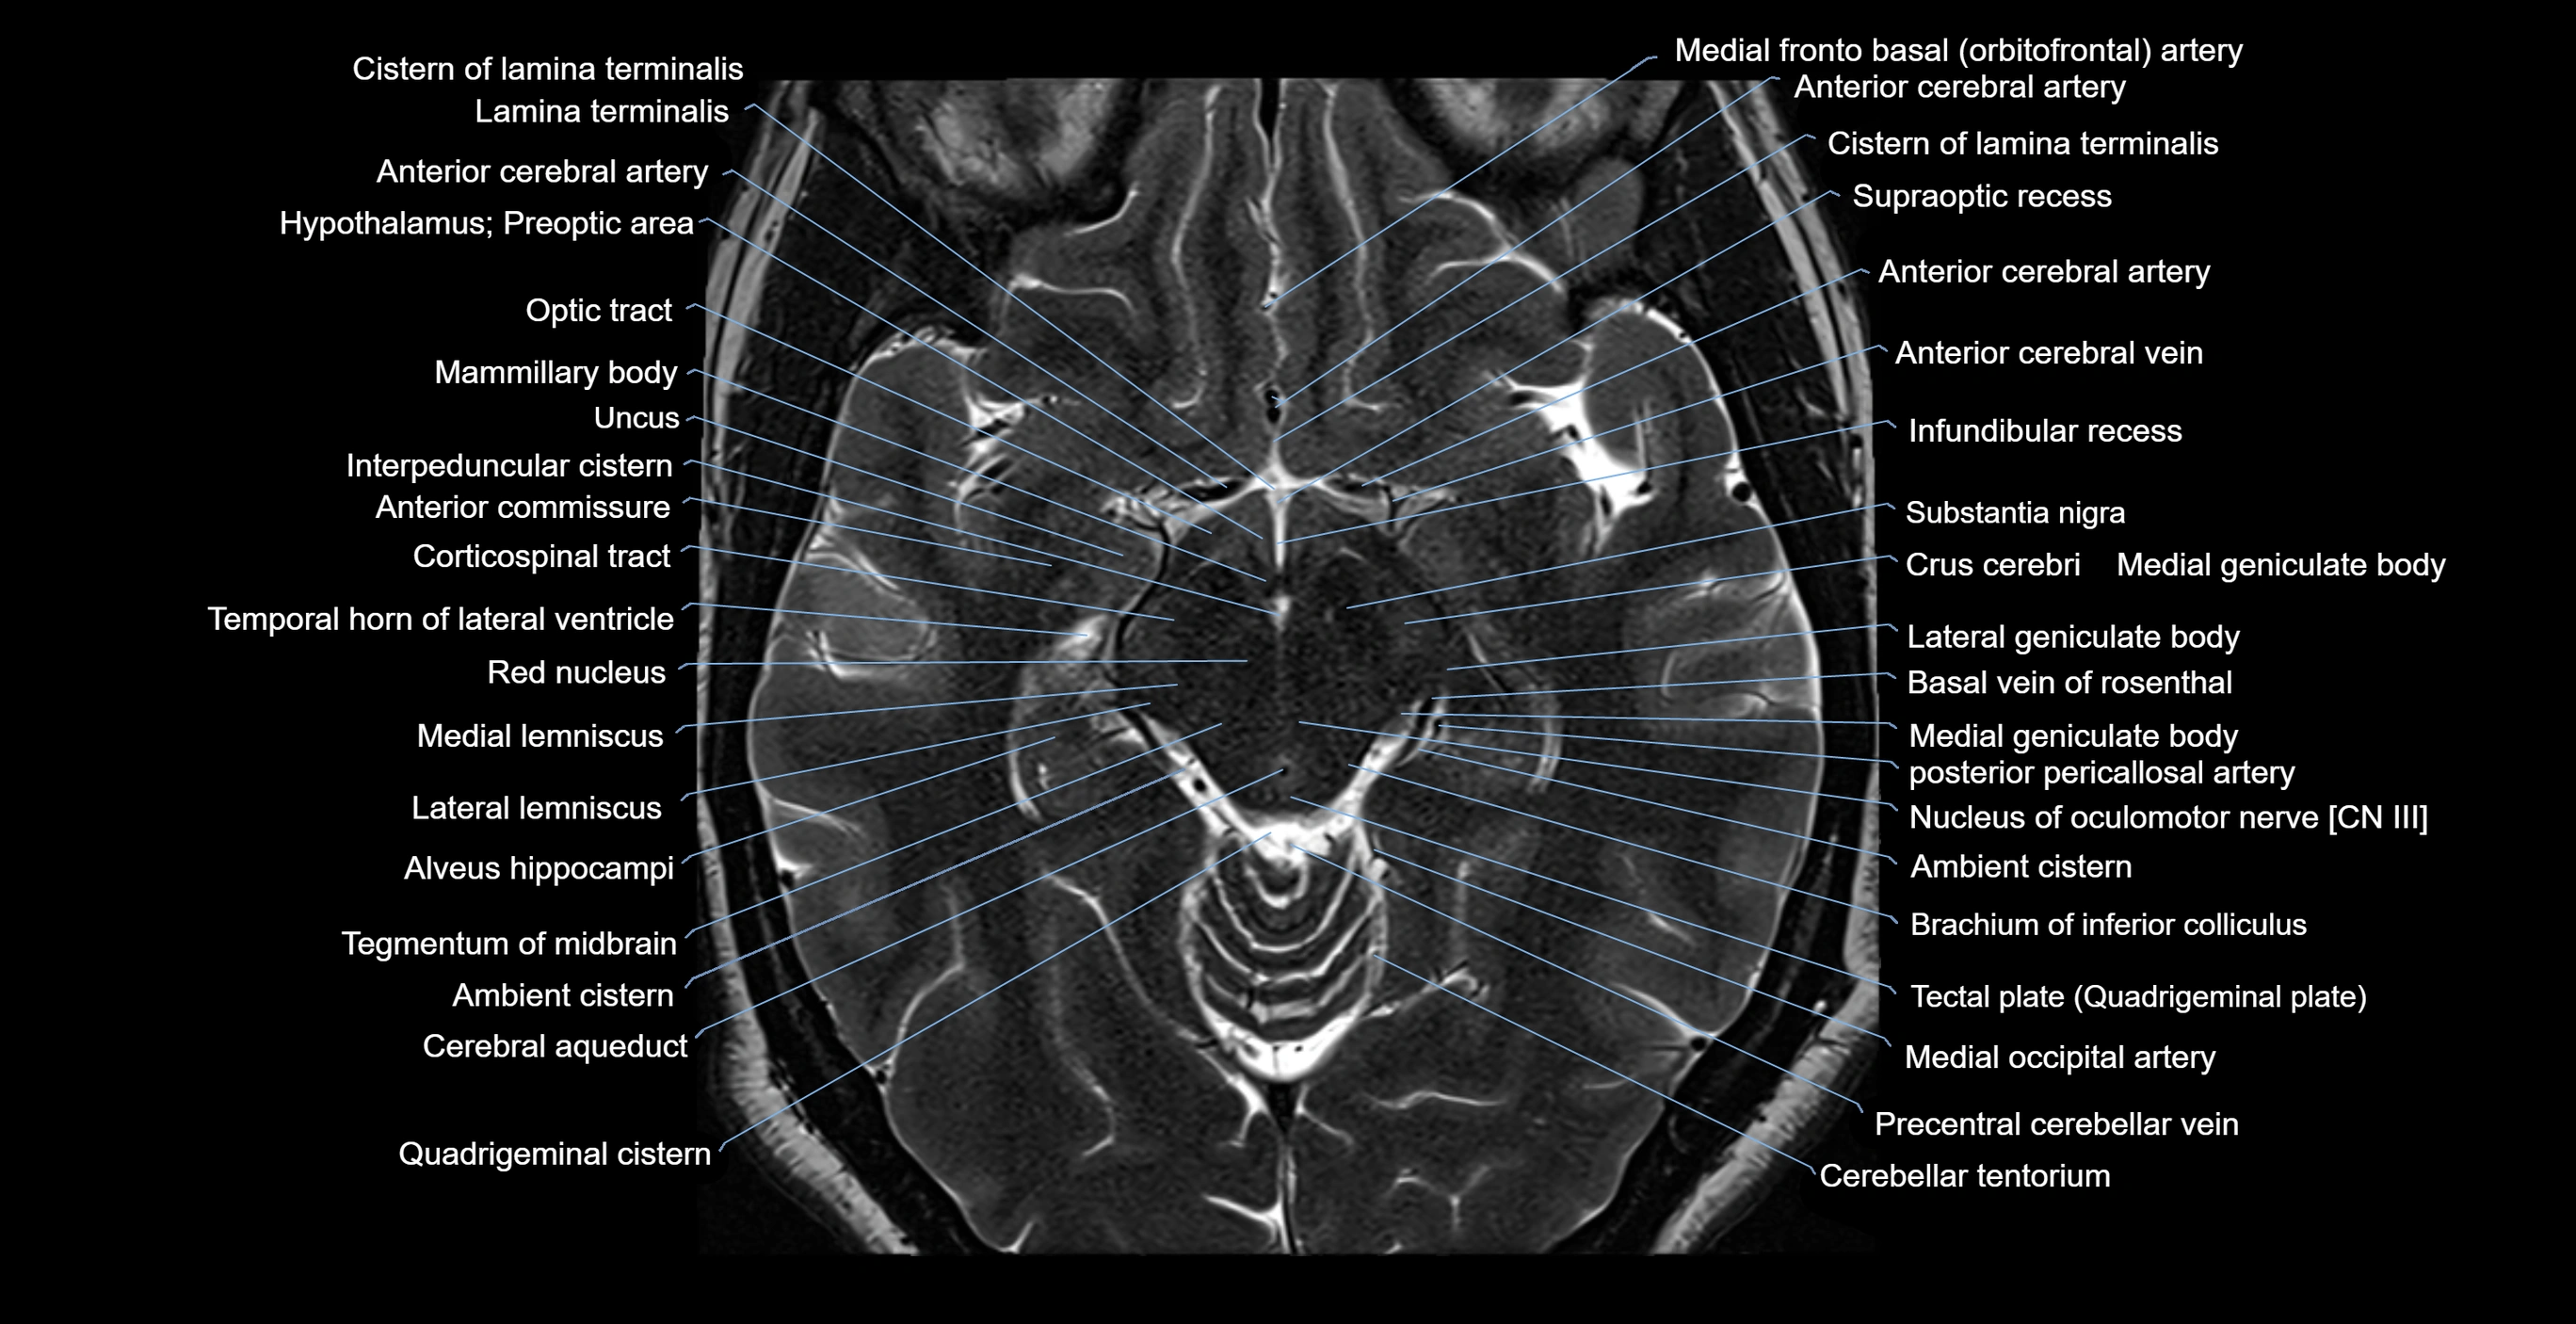

MRI images